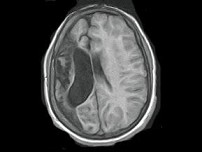

男,35岁,有颅脑外伤史,MRI图像,最可能的诊断是()

• A.脑软化

• B.脑萎缩

• C.脑积水

• D.脑穿通畸形囊肿

• E.脑实质占位